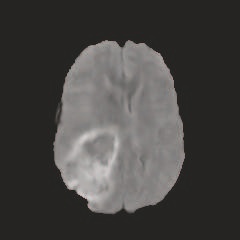

Multi-modal medical image completion has been extensively applied to alleviate the missing modality issue in a wealth of multi-modal diagnostic tasks. However, for most existing synthesis methods, their inferences of missing modalities can collapse into a deterministic mapping from the available ones, ignoring the uncertainties inherent in the cross-modal relationships. Here, we propose the Unified Multi-Modal Conditional Score-based Generative Model (UMM-CSGM) to take advantage of Score-based Generative Model (SGM) in modeling and stochastically sampling a target probability distribution, and further extend SGM to cross-modal conditional synthesis for various missing-modality configurations in a unified framework. Specifically, UMM-CSGM employs a novel multi-in multi-out Conditional Score Network (mm-CSN) to learn a comprehensive set of cross-modal conditional distributions via conditional diffusion and reverse generation in the complete modality space. In this way, the generation process can be accurately conditioned by all available information, and can fit all possible configurations of missing modalities in a single network. Experiments on BraTS19 dataset show that the UMM-CSGM can more reliably synthesize the heterogeneous enhancement and irregular area in tumor-induced lesions for any missing modalities.